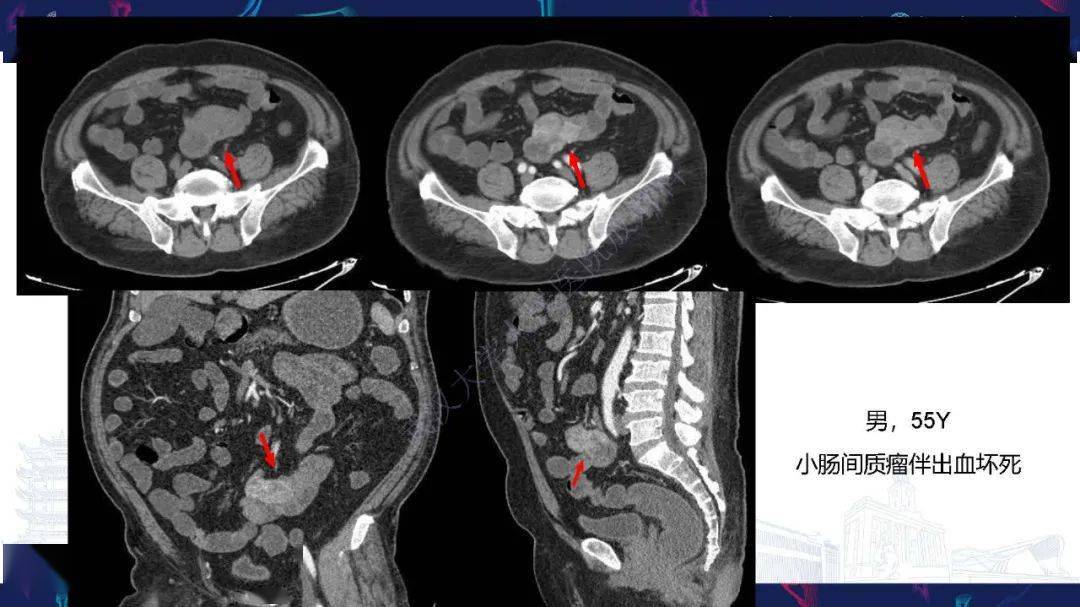

直肠胃肠道间质瘤影像诊断